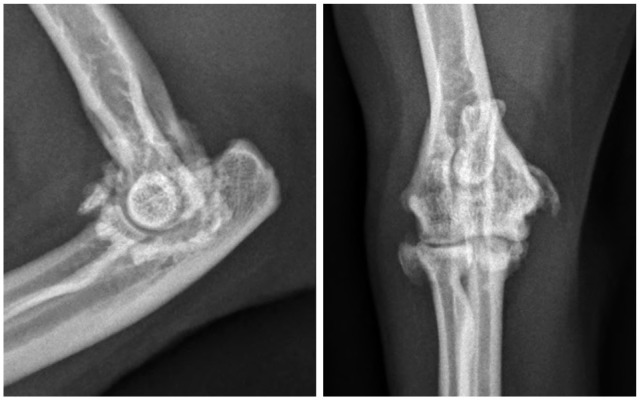

本研究的目的是描述患有内侧肱骨上髁炎(MHE)的猫的临床表现、诊断结果和非手术和手术治疗的反应。我们检索了一家机构的医疗记录,寻找经放射学证实诊断为MHE的猫,这些猫单独进行非手术治疗或同时进行非手术和手术治疗。包括9只猫(17只肘部)。这些猫都没有户外活动的记录。骨科检查显示触诊内侧上髁疼痛(n = 15),肘关节旋前(n = 7)或腕屈曲(n = 7),内侧上髁远端可触及矿化(n = 7)。上髁炎放射学分级为轻度(n = 8)、中度(n = 7)和重度(n = 2)。在10个肘部进行了CT检查,在7个肘部发现了额外的信息,包括5个肘部的关节内矿化体。在四个肘部进行超声检查,发现尺侧腕屈肌周围有液体。非手术治疗后,4只猫无反应,4只猫部分反应,1只猫完全反应。放射学变化不那么严重的猫似乎表现出更有利的反应。4只猫(7只肘部)接受了手术治疗,所有猫都有明显的尺神经炎。3只猫(5只肘部)术后跛行消失。隐伏的中度跛行与触诊疼痛相关的内上髁尾远端疼痛应该增加MHE的怀疑指数,并及时评估是否存在可触及的矿化和腕屈疼痛。尺神经炎是常见的猫与MHE,他们经常出现游离关节矿化体。x线摄影只能检测晚期或慢性MHE,此时非手术治疗可能无效。早期超声诊断可改善非手术治疗后的预后。

Case series summary The aim of this study was to describe the clinical findings, diagnostic results and response to both non-surgical and surgical therapy in cats with medial humeral epicondylitis (MHE). The medical records of one institution were searched for cats with a radiographically confirmed diagnosis of MHE where non-surgical therapy alone or both non-surgical and surgical therapy had been trialed. Nine cats (17 elbows) were included. None of the cats had a history of outdoor access. Orthopedic examination revealed pain upon palpation over the medial epicondyle (n = 15), elbow pronation/supination (n = 7) or carpal flexion (n = 7) and palpable mineralization distal to the medial epicondyle (n = 7). Epicondylitis was radiographically graded as mild (n = 8), moderate (n = 7) or severe (n = 2). CT was performed in 10 elbows and revealed additional information in seven, including intra-articular mineralized bodies in five elbows. Ultrasound was performed in four elbows and revealed fluid surrounding the flexor carpi ulnaris muscle. After non-surgical management, four cats showed no response, four showed a partial response and one showed a complete response. Cats with less advanced radiographic changes appeared to show more favorable responses. Four cats (seven elbows) underwent surgical treatment with ulnar neuritis being evident in all. Lameness resolved postoperatively in three cats (five elbows).Relevance and novel information An insidious onset of moderate-grade lameness associated with pain on palpation caudodistal to the medial epicondyle should increase the index of suspicion for MHE and prompt assessment for the presence of palpable mineralization and pain on carpal flexion. Ulnar neuritis is common in cats with MHE and they frequently present with free articular mineralized bodies. Radiographs can only detect advanced or chronic stages of MHE, by which time non-surgical management is likely to be ineffective. Earlier diagnosis using ultrasound may improve the prognosis after non-surgical management.